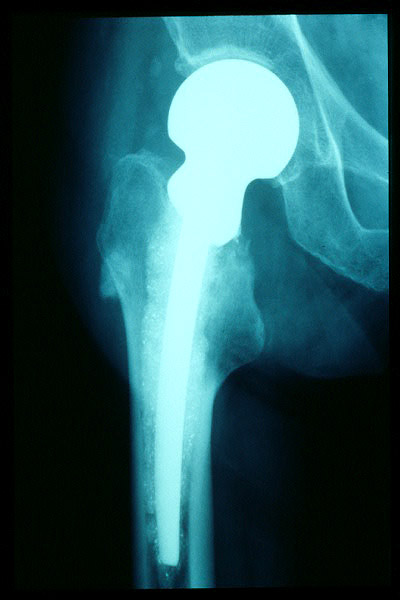

Fractura cuello fémur. Prótesis completa.

Fractura de fémur, prótesis parcial de cadera

Prótesis parcial de cadera

Prótesis de cadera.